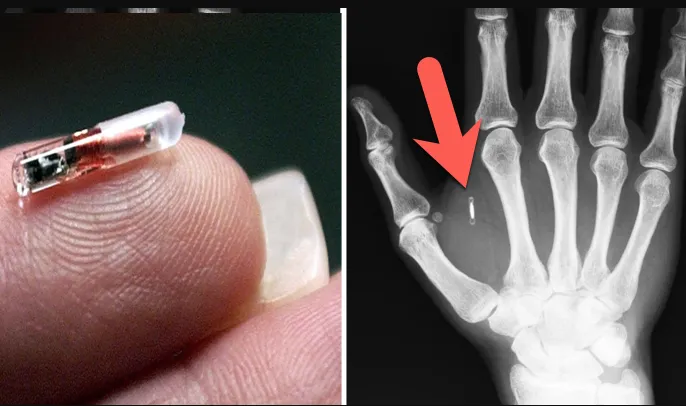

Đây là thời đại vô cùng hiện đại, ngay cả người máy AI gia dụng cũng có thể vào Starnet như con người, qua đó thực hiện các tác vụ tương ứng hoặc mua sắm thay chủ nhân của mình, tất cả chỉ cần một con chip điện tử đã qua chứng nhận mà thôi.

Mặc dù An Minh Hối cảm thấy Liên Bang sẽ không bao giờ cấp chứng nhận cho con chip của mình, nhưng Lair vẫn lắp cho anh một con chip đã được chứng nhận. Điều này khiến anh cảm thấy ở một số phương diện đặc biệt đối phương quả thực rất thần bí.

(*) Chú thích: Chip điện tử (Microchip) là một vi mạch nhỏ hơn hạt gạo một chút được cấy bên dưới da có tác dụng định danh, hiện nay chủ yếu dùng cho chó mèo nhưng cũng có một số quốc gia/công ty cấy trên người. Trong bối cảnh tương lai của truyện chắc Microchip tác giả nhắc đến phổ biến rộng và có chức năng như chứng minh thư, thậm chí kiêm luôn chức năng của thẻ ngân hàng, giấy tờ tùy thân khác.